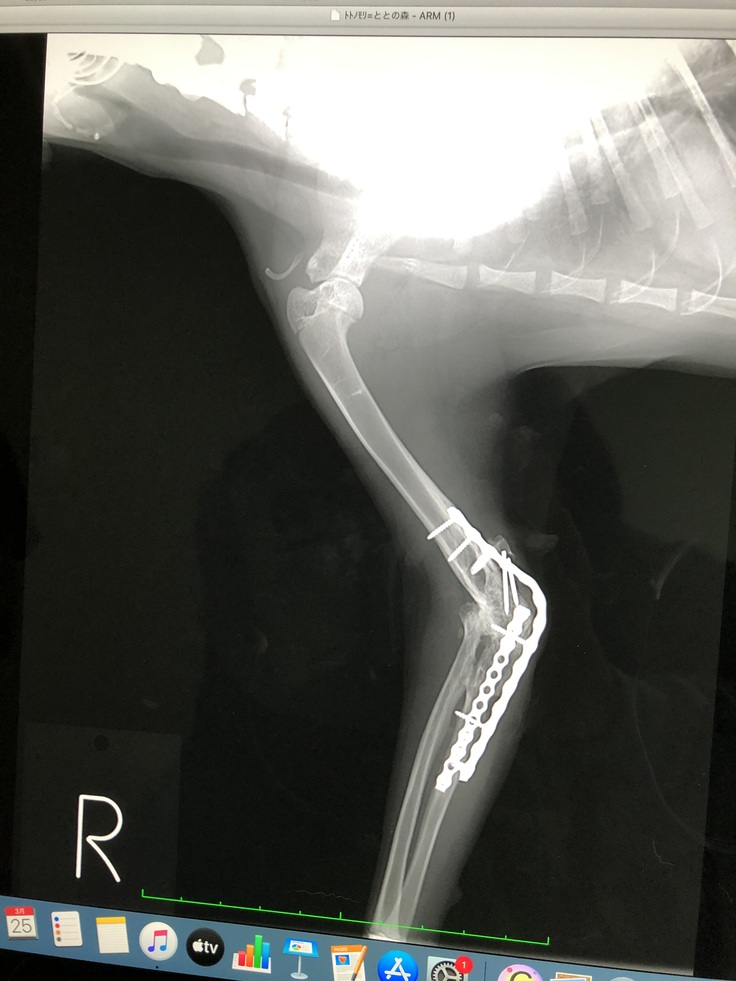

(のの2回目の前足金具装着手術)